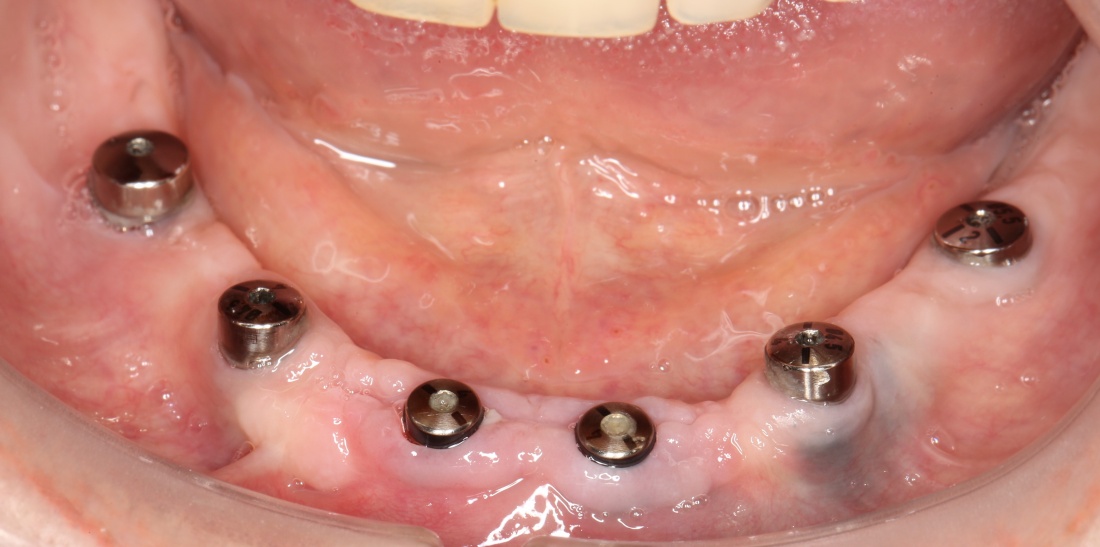

Простой пример. Возьмём один и тот же клинический случай — полную потерю зубов вследствие удаления на одной из челюстей. Что-то типа этого:

И вот представьте, что с подобной клинической картиной обращаются два человека.

Один из них — 45-летний мужчина, который, буквально, потерял все зубы разом из-за пародонтита.

Второй пациент — 80-летняя бабушка, большую часть своей жизни пользующаяся полным съёмным протезом. Какие имплантологические решения мы им предложим и от чего они будут зависеть? Ведь вариантов достаточно много.

Что мы ему предложим? Разумеется, несъемное протезирование с опорой на 6-8 имплантатов:

80-летняя бабушка жалуется на то, что у неё съемный протез выпадает, ей перед подругами по лавочке стыдно. И она ожидает, что мы придумаем какую-нибудь штуку, которая поможет её протезу держаться на челюсти и не выпадать.

Скажите, каким будет оптимальное решение в её случае? 2 импланта, шариковые абатменты или локаторы:

Просто фиксируем существующий протез к имплантам — и всё! Бабушка счастлива!

А что будет, если мы случайно перепутаем, и предложим 45-летнему мужику съемный протез на локаторах, а бабушке 6-8 имплантатов с керамическим несъемным протезом? В лучшем случае, нас просто пошлют на хрен, в худшем — это будет выглядеть как некомпетентность и развод на бабки, в наихудшем — об этом еще все узнают.